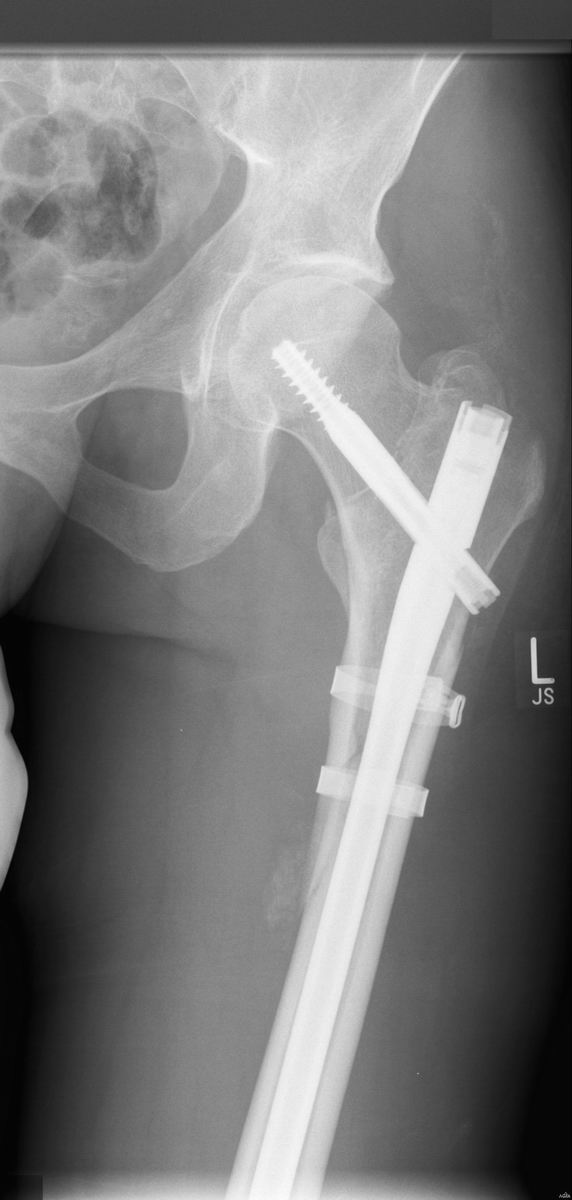

Heute habe ich von der Žrztin die CD mit nicht weniger als 19, davon 13 Röntgen-, Bildern meines linken Beines von der Žrztin zurück erhalten. Wenn ich dazu die zahlreichen Beschüsse meiner linken Hand mit Röntgenstrahlung aus der Vergangenheit bedenke, könnte ich ja direkt mal über einen halbwegs passenden Wechsel meines Avatars nachdenken

Da ich den Röntgenbild-Thread nicht mehr finde, an dieser Stelle eine kleine Auswahl.

Das letzte Bild könnte auch vom Terminator stammen